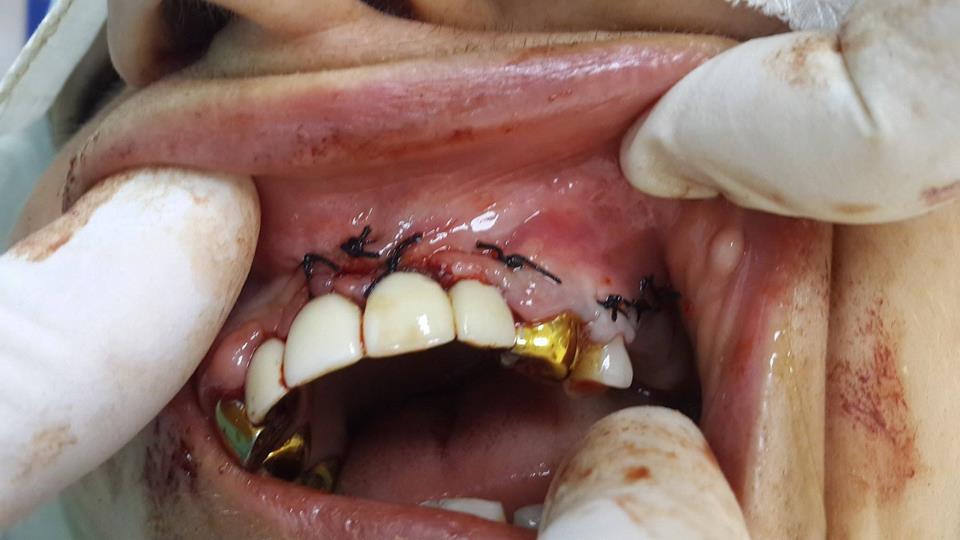

The patient turned to the doctor with the presence of a retinas tooth. The tooth was surgically removed.